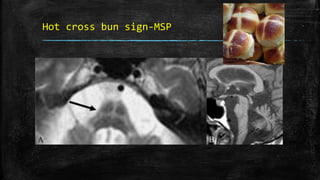

Hot cross bun sign-MSP

• #105 Hot cross bun sign. Axial T2W MRI image of the pons (A) in a patient with multiple system atrophy shows a hyperintense linear area forming a ‘cross’ (arrow) in the pons. Sagittal T1W image (B) shows atrophy of the cerebellum and cerebrum (prominence of sulci)